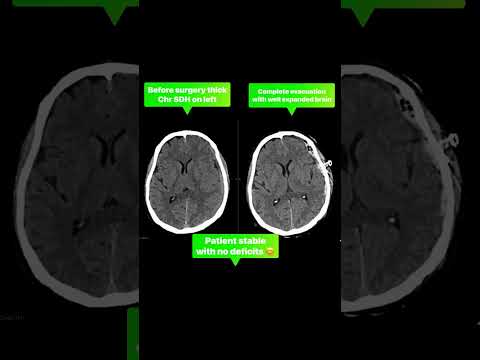

This real-life patient testimonial shares the inspiring recovery journey of a young boy who met with a road accident after being hit by a motorcycle. He was unconscious and in critical condition, but with timely medical intervention and expert care, he made a remarkable recovery. In this video, you will learn: ✔️ What happens during a road traffic accident injury ✔️ Importance of immediate medical care ✔️ Treatment and surgical process ✔️ Recovery journey after trauma ✔️ Life after treatment Road accidents can be life-threatening. Early treatment can save lives.